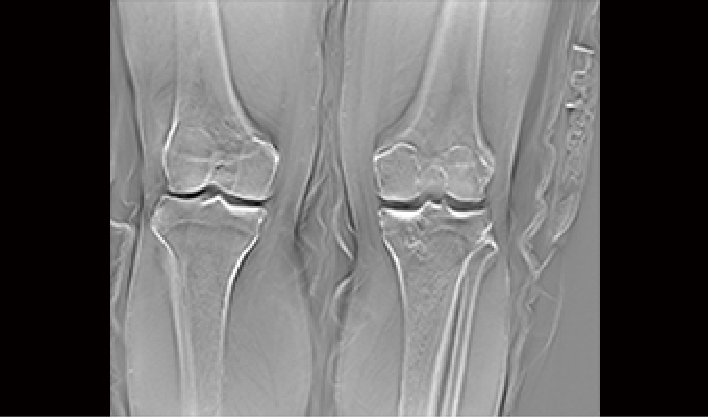

大功率高热容量,确保连续动态观察器官

1450mm大行程运动,满足全身影像链覆盖